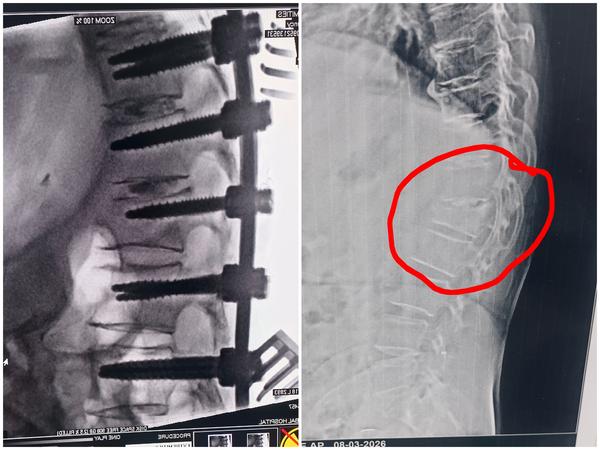

Best Spine Surgeon in Pune Best Spine Specialist in Pune Dr. Nitish Agarwal

View Details